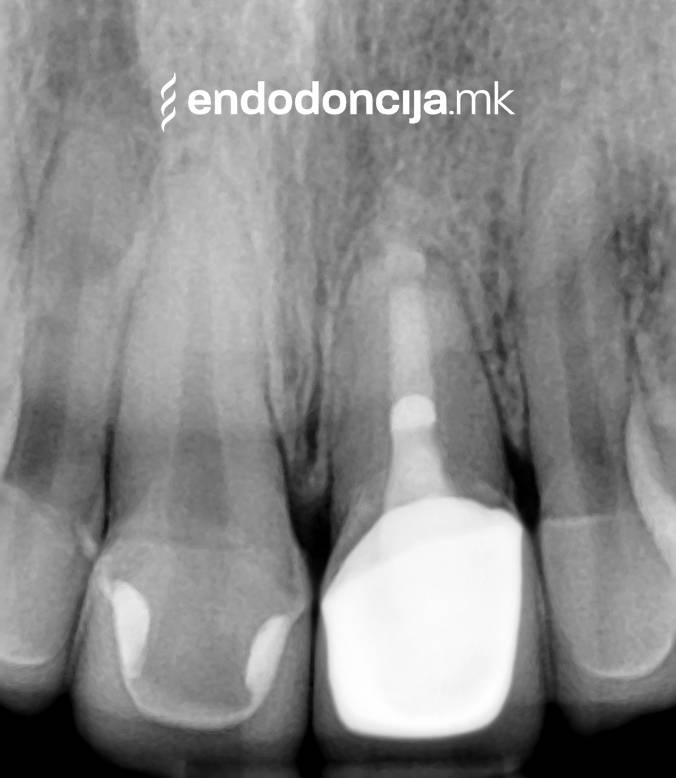

Σε περίπτωση ανανέωσης της θεραπείας του ριζικού καναλιού (αναθεώρηση) παλιά γεμίσματα ρίζας που δεν ήταν επιτυχημένα και ως εκ τούτου ήταν η αιτία φλεγμονών και πόνου, μπορούν να αφαιρεθούν και να ανανεωθούν εξειδικευμένα. Αυτή η θεραπεία εξαλείφει τις φλεγμονές στην περιοχή της ρίζας και καθίσταται δυνατή η πλήρης ανάρρωση.

Κατά τη διάρκεια προηγούμενων θεραπειών, το δόντι μπορεί όχι μόνο να έχει αποδυναμωθεί από τη μηχανική επεξεργασία του ριζικού σωλήνα αλλά και από τη στερέωση και την αγκύρωση ενός ρίζα. Όταν αναθεωρείται η επεξεργασία ενός ριζικού καναλιού, αυτοί οι πείροι πρέπει να αφαιρούνται όσο το δυνατόν πιο προσεκτικά για να διατηρούν σημαντική ουσία των δοντιών.